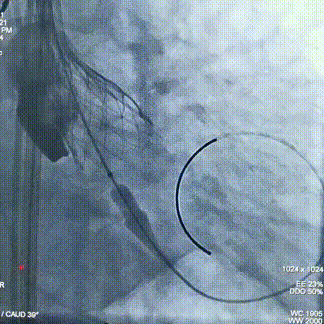

球囊预扩

瓣膜定位

经评估后植入左主干烟囱支架